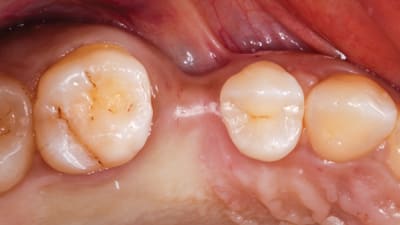

Clinical Technique Review Implantology Osseodensification Effective for Immediate Molar Replacement By Rodrigo Neiva, DDS, Salah Huwais, DDS, Samvel Bleyan, DDS July 15, 2022 13 min read